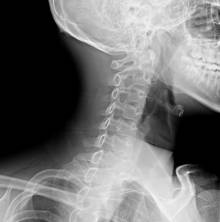

Шейный остеохондроз

Наиболее распространённая причина дискомфортного состояния. Почему возникает боль? Позвонки соединены дисками, состоящими из хрящевой ткани. С возрастом или при постоянных физических перегрузках, межпозвоночные диски истончаются, нарушается амортизация при движении, позвонки соприкасаются друг с другом. По всей протяжённости позвоночного столба проходят кровеносные сосуды и нервы. Когда хрящ изнашивается, позвонки защемляют нервные окончания, что и способствует развитию болевого синдрома. При остеохондрозе болит затылок, немеют кончика пальцев на руках, ноет плечо, хрустит шея. Повороты головы становятся ограниченными.

Что назначают для спасения от заболевания опорно-двигательного аппарата? Остеохондроз не лечится, можно, лишь при обострениях снизить интенсивность болей и принять все меры по профилактике.